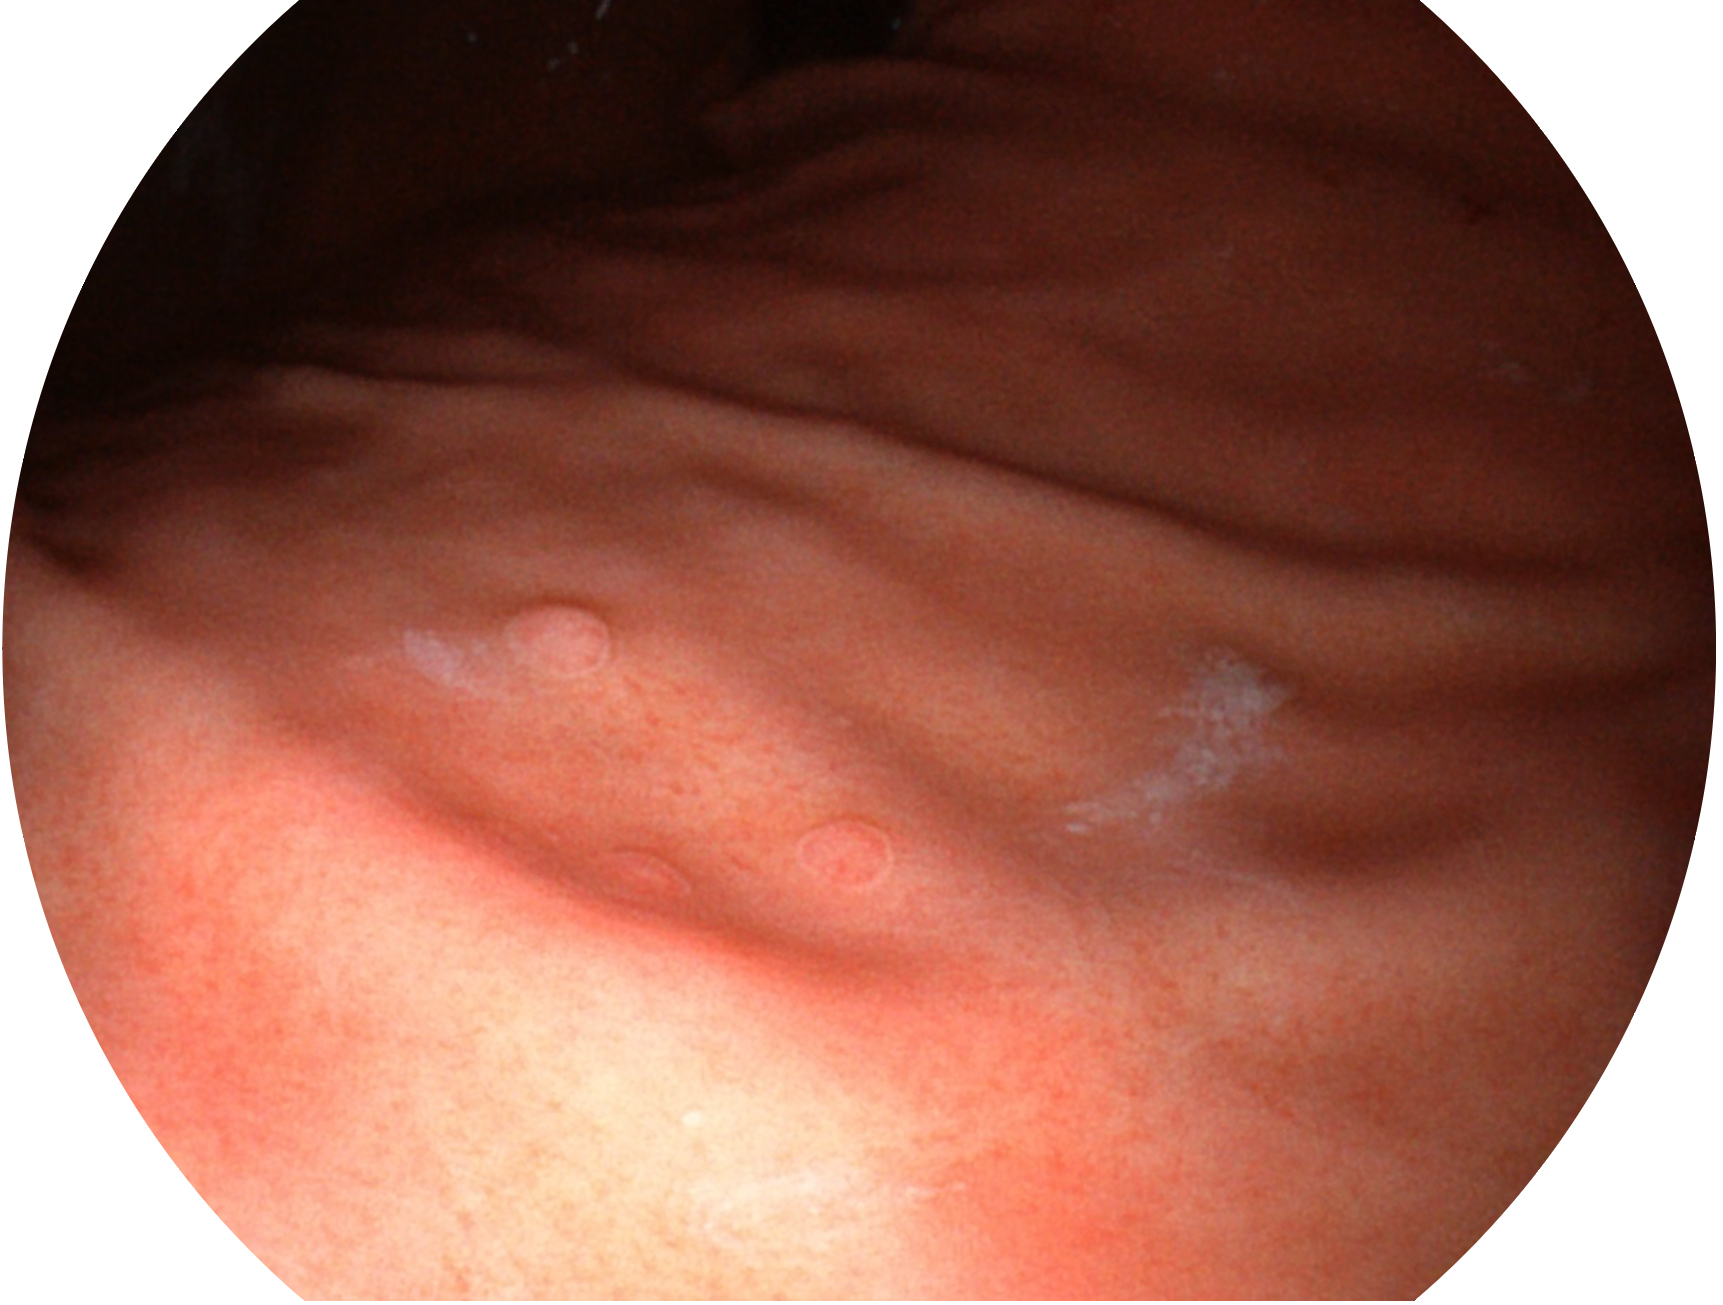

新葡的京集团8814检测站新开发的内镜染色技术,主要是基于多波长LED 光源的开发,VLS-55Q 四波长LED 光源是由四个不同颜色的LED光按照相应照明模式所规定的特定发光比例进行合束后形成,合束后形成的照明光的光谱由红光、绿光、蓝光及蓝紫光这四个不同的波段范围构成。具有更高光谱自由度,通过光谱比例的控制,实现了聚谱成像技术,英文全称为“Spectral Focused Imaging, SFI”,缩写为“SFI”和光电复合染色成像技术,英文全称为“Versatile Intelligent Staining Technology, VIST”,缩写为“VIST”。